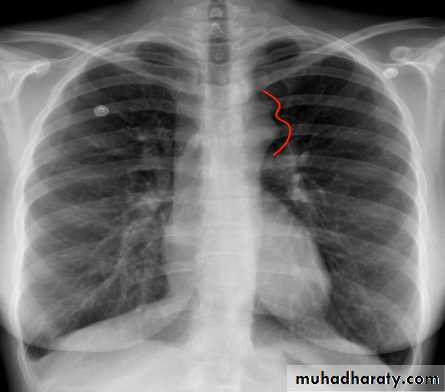

In older children: the ECG and chest x-ray usually show LVH and a mildly enlarged heart. Rib notching may also be seen in older children (>8 years of age) with large collaterals. Echocardiography shows the site and degree of coarctation, presence of LVH, and aortic valve morphology and function.

3 sign of aorta Rib notching

(Post stenotic dilation of aorta)